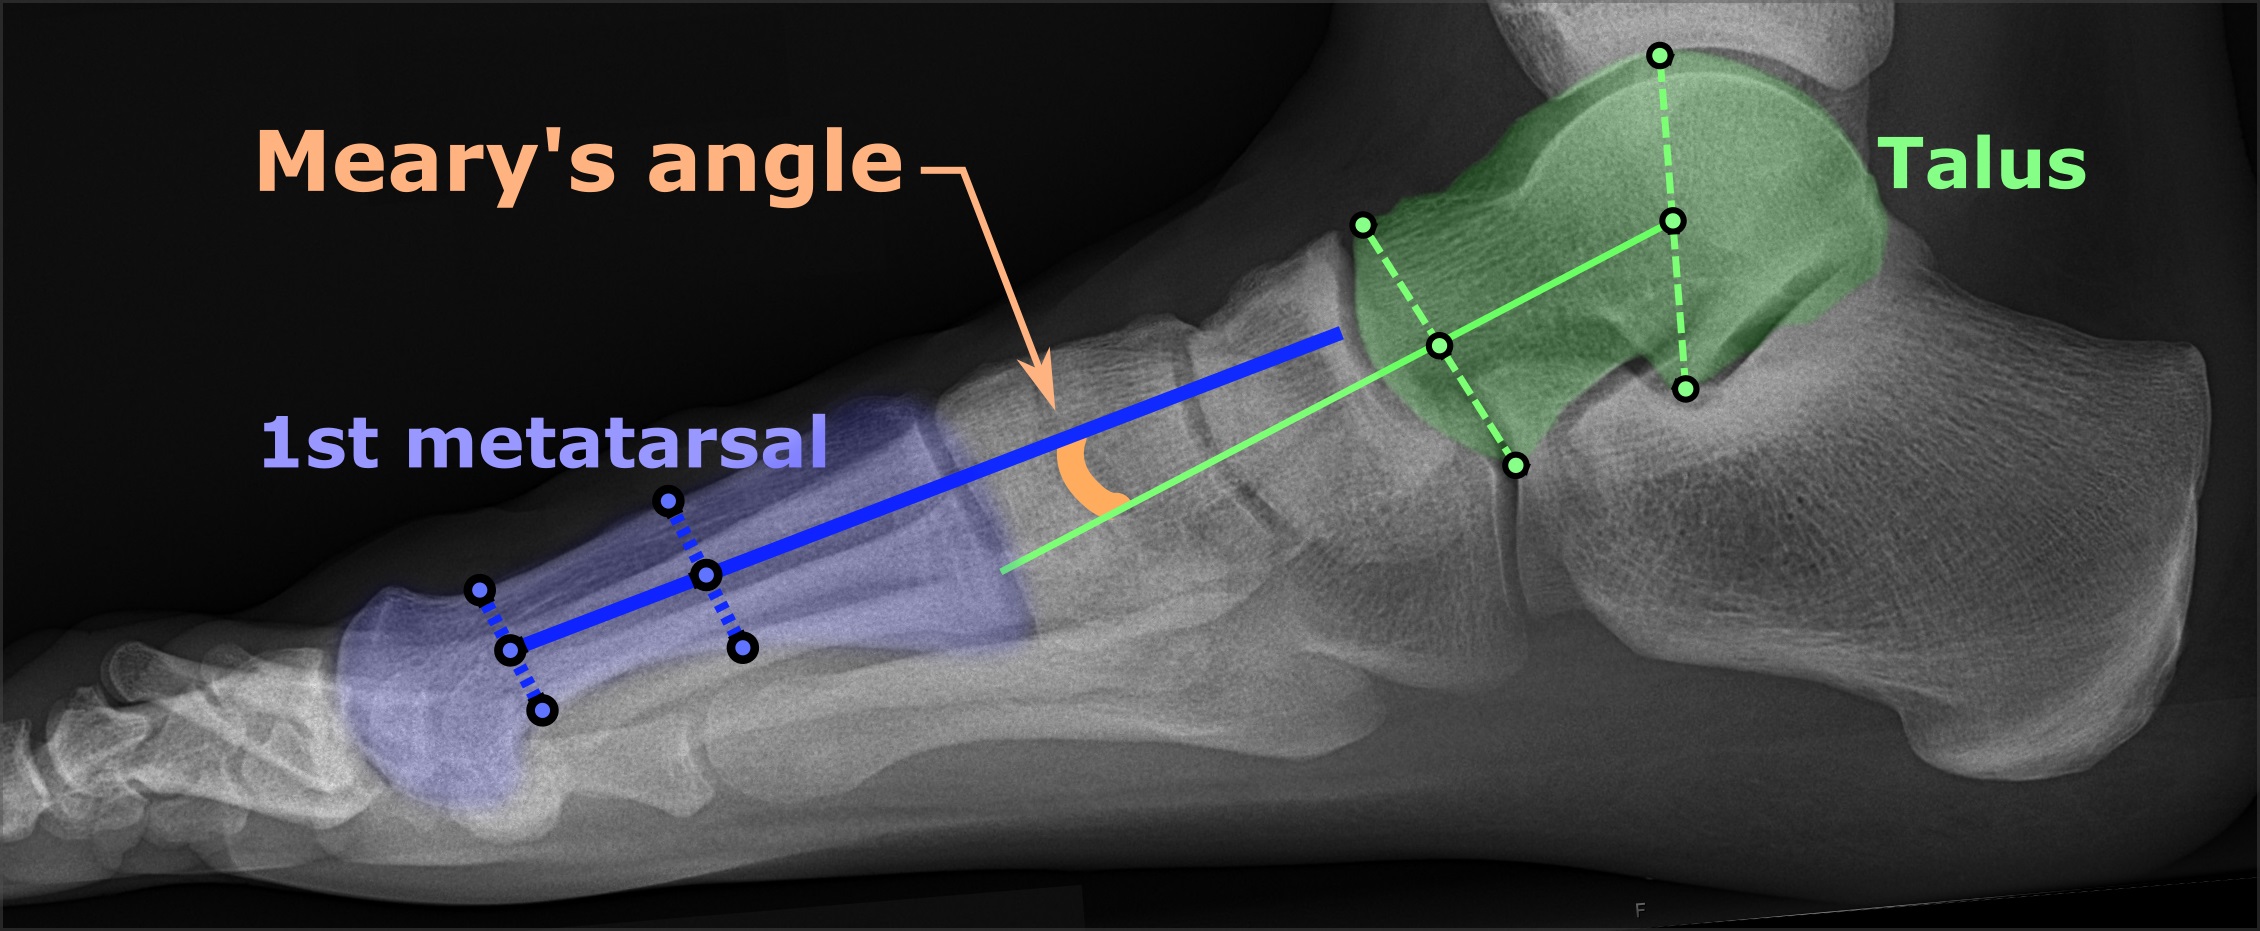

Talocalcaneal angle(30-55도, dorsiflexion lat시 25~50도) 이나 Talo-1st MT angle(5-15도), tibiocalcaneal stress lateral angle(10~40도) 를 시행해 볼 수 있습니다.

Talocalcaneal angle은 AP에서 Kite angle 로 불리는데, 만곡족시 후족부가 내반될 경우 30도 이하가 됩니다. (cf. 외반일경우 55도 이상)

Talocalcaneal angle은 Lat 에서 감소하거나 음각이 되기도 합니다.

Talo-1st MT angle은 전족부의 내전을 평가하는 수치로, 만곡족에서는 음각 입니다.